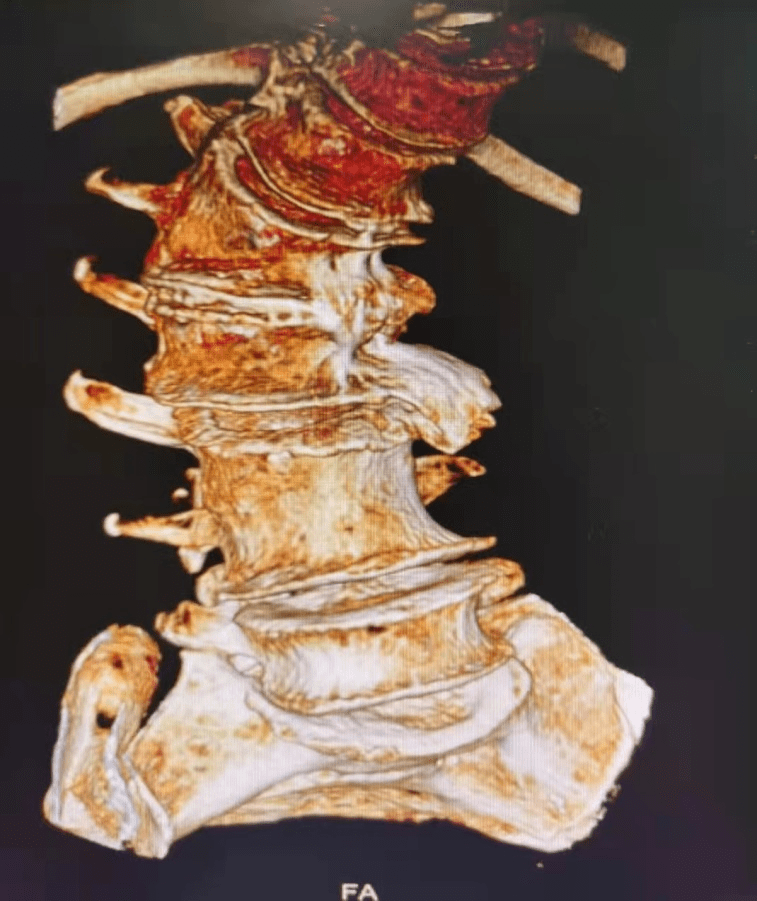

那么李阿姨的腰椎到底弯到了什么程度呢?大家可以看一下:

文章图片

第二 , 光是脊柱侧弯导致走路不好看也就算了 , 最关键是脊柱侧弯导致严重的椎间盘突出、骨质增生 , 身体形态改变导致髋关节、膝关节受力改变 , 慢慢的都出现关节变形 , 腰疼、髋关节疼痛、膝盖痛的毛病一个跟着一个都来了 。

其中最难熬的就是腰疼 , 腰椎是人体负责承上启下的主要结构 , 其中相关的血管、神经、肌肉不计其数 , 李阿姨的腰椎侧弯非常严重 , 还是扭转弯的那种 , 就跟拧了个麻花似的 , 可以想象里面的神经都被压成什么样子了 。